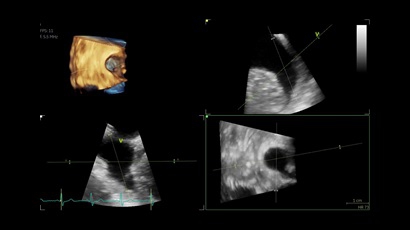

• Vivid IQ 4D с поддержкой технологии объемной реконструкции

• Передовые технологии, такие как 4D чреспищеводная эхокардиография, ЭКГ, стресс-эхо, внутрисердечная ультразвуковая эхокардиография, тканевый доплер и другие.

• Режимы: 4D, 2D (B-режим), цветной допплеровский режим, режим энергетического допплера, M-режим, цветной M-режим, спектральные режимы импульсно-волнового допплера (PW) и непрерывно-волнового допплера (CW), визуализация скорости движения тканей.

• 4D AUTO AVQ - модуль автоматического выравнивания, сегментации и обсчета размеров кольца аортального клапана по объемным данным.

• 4D AUTO LVQ - модуль расчета массы миокарда ЛЖ на основе данных 4D-исследования.